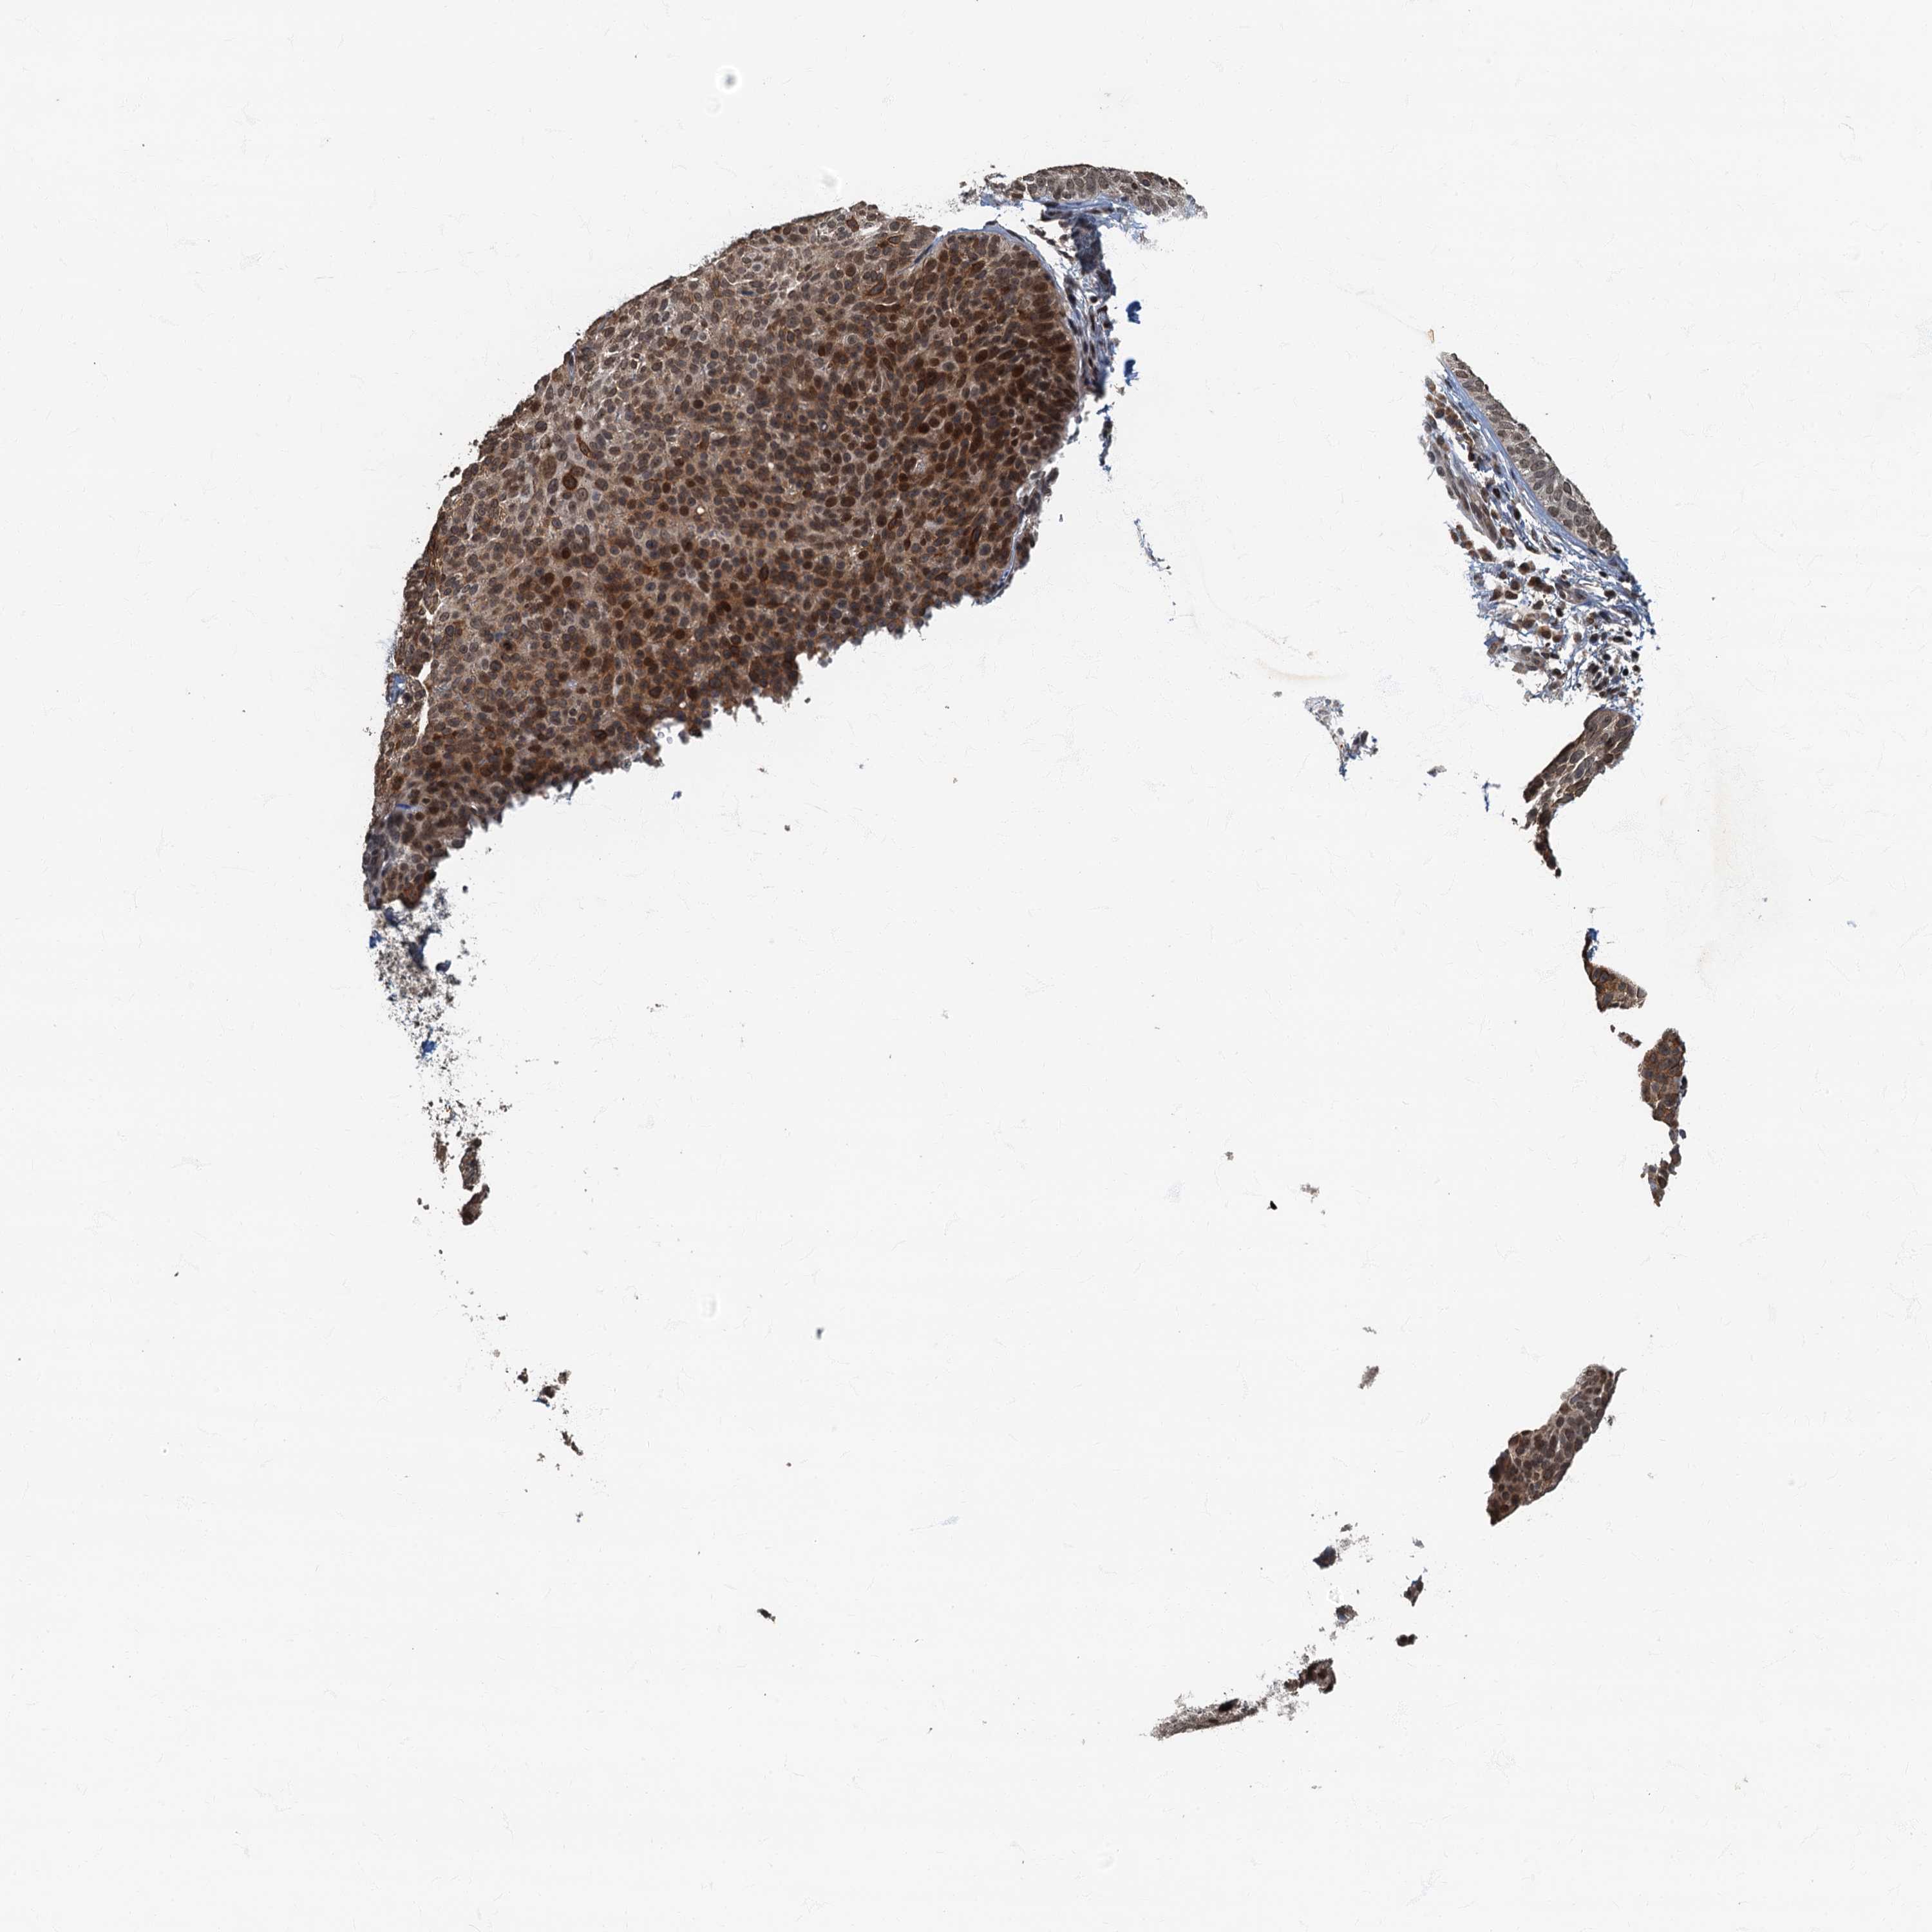

SKIN CANCER - Protein expressioni

A mouse-over function shows sample information and annotation data. Click on an image to view it in a full screen mode. Samples can be filtered based on level of antibody staining by selecting one or several of the following categories: high, medium, low and not detected. The assay and annotation is described here.

Antibody stainingi

Antibody staining in the annotated cell types in the current human tissue is reported as not detected, low, medium, or high, based on conventional immunohistochemistry profiling in selected tissues. This score is based on the combination of the staining intensity and fraction of stained cells.

Each image is clickable and will lead to virtual microscopy that enables deeper exploration of all samples and also displays staining intensity scores, fraction scores and subcellular localization as well as patient and tissue information for each sample.

Antibody HPA039407

Antibody HPA040057

Staining

High

Medium

Low

Not detected

Intensity

Strong

Moderate

Weak

Negative

Quantity

>75%

75%-25%

<25%

None

Location

Nuclear

Cytoplasmic/membranous

Cytoplasmic/membranous,nuclear

Basal cell carcinoma